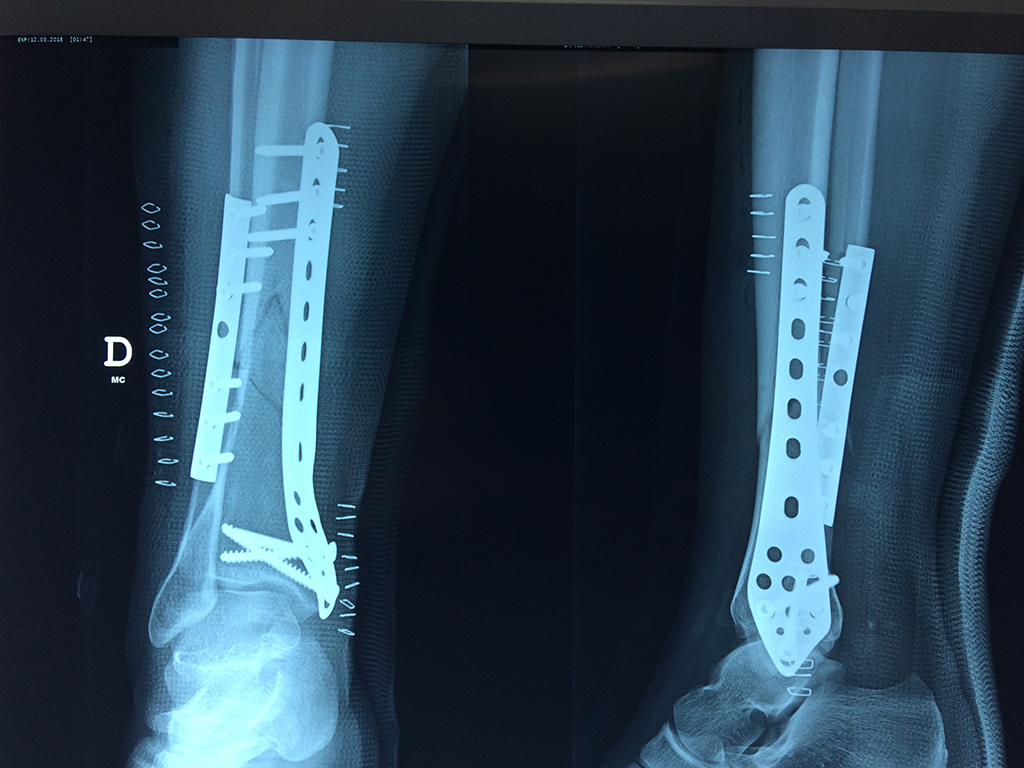

La mayor parte de las roturas implican a la parte proximal del hueso (parte del hueso próximo a la rodilla) o a la parte distal (parte del hueso cerca del tobillo).